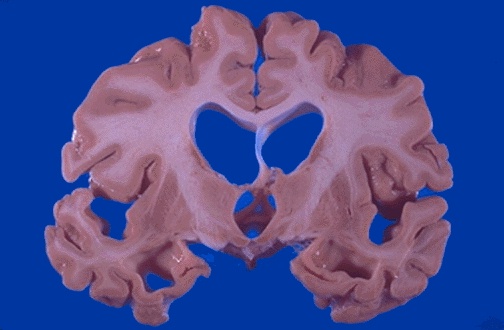

Image 3.1

This is the gross appearance of the brain from a man who died from the same disease suffered by this patient.